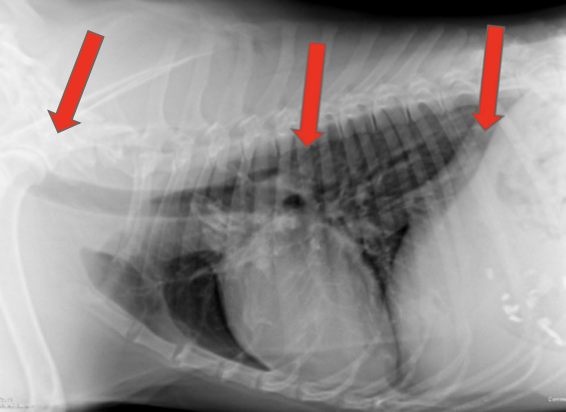

how is megaesophagus diagnosed?

-cervical and thoracic radiographs +/- oral contrast

how are hiatal hernias diagnosed?

may manifest intermittently

-thoracic radiographs: caudodorsal, gas-filled intrathoracic soft-tissue opacity

-contrast videofluoroscopy swallow study (normal does not rule out a hiatal hernia)